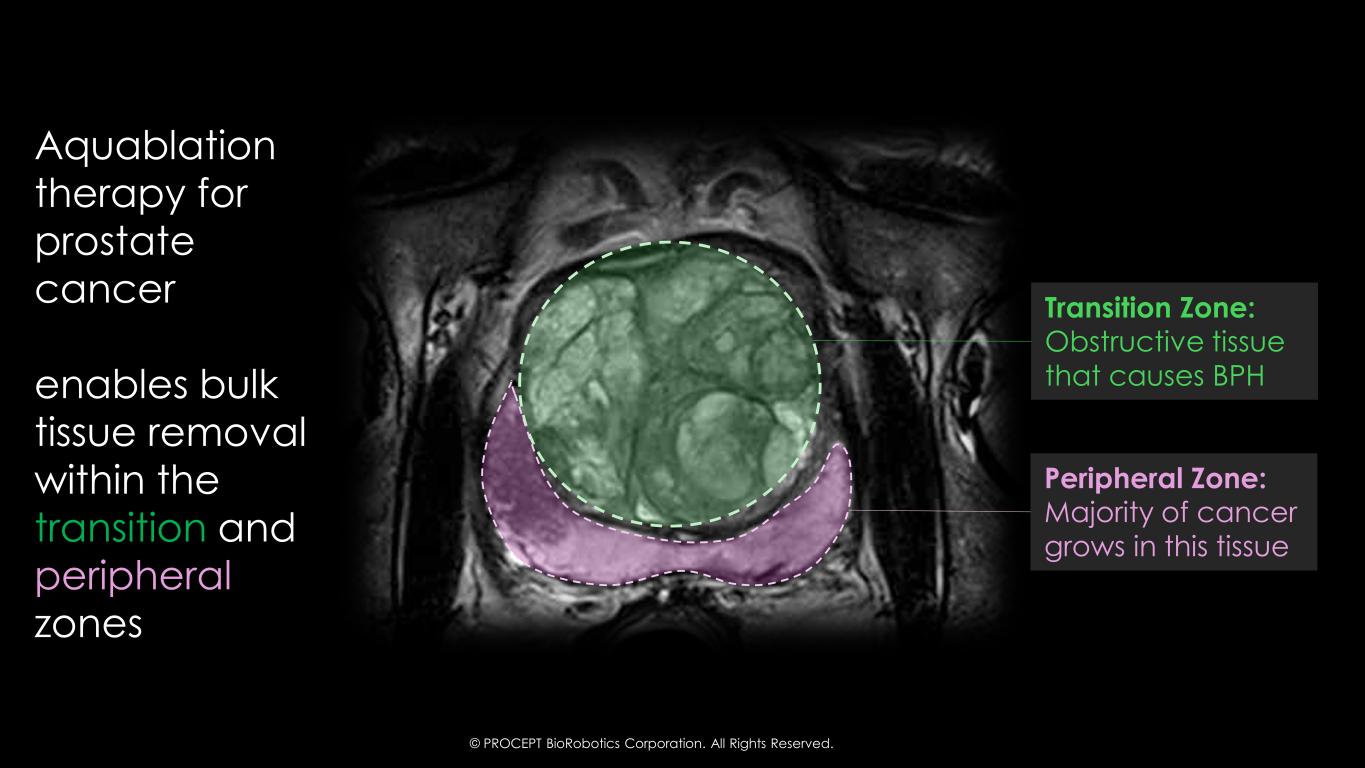

33 Aquablation therapy for prostate cancer enables bulk tissue removal within the transition and peripheral zones Transition Zone: Obstructive tissue that causes BPH Peripheral Zone: Majority of cancer grows in this tissue © PROCEPT BioRobotics Corporation. All Rights Reserved.

34 Aquablation Therapy Prostate Cancer Summary Today’s Key Message 1 Prostate Cancer is a multi-focal disease that requires a whole gland treatment 3 Aquablation therapy can treat the peripheral zone 2 Strong confidence in WATER IV trial design assumptions 4 60% of Active Surveillance patients will undergo radical treatment in 10-15 years1 © PROCEPT BioRobotics Corporation. All Rights Reserved. To receive FDA-IDE approval to enroll randomized trial comparing surgical therapy vs. radical prostatectomy To pursue a specific treatment indication for prostate cancer First Company Ever… 1. Hamdy et al N Engl J Med 2023 AND

54 Prostate Cancer is a Not A Focal Disease MISCONCEPTION Aquablation Therapy is Focal Therapy… Aquablation Therapy results in a Near Total Resection of the prostate 1 Waterjet has access to Transitional & Peripheral Zone 2 Ability to resect >95% of all prostate tissue 3 Near Total Resection preserves prostate capsule, resulting in better safety outcomes 40% of Significant Cancers are Underestimated by MRI1 © PROCEPT BioRobotics Corporation. All Rights Reserved. 1. Johnson et al Cancer 2019